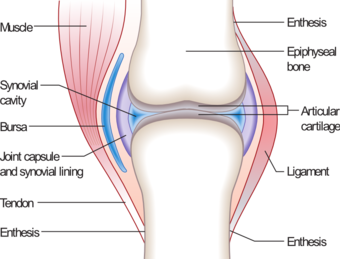

Typical joint | |